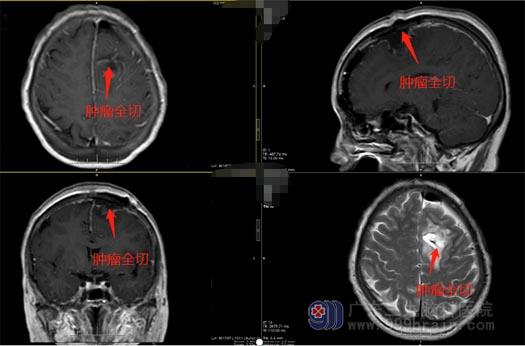

在与患者家属沟通后,手术由王国良主任主刀,他带领神经外五科专业团队为陈某在全麻下行“左侧额部大脑镰窦旁脑膜瘤切除术”,术中镜下全切肿瘤,手术顺利结束,术后恢复自主呼吸,生命体征平稳,经专科治疗狐护理,一周后陈某康复出院。

▲术后